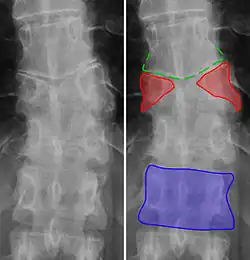

Butterfly vertebrae

Butterfly vertebra (red). Normal vertebra for comparison (blue).

Butterfly vertebra (red). Normal vertebra for comparison (blue). -